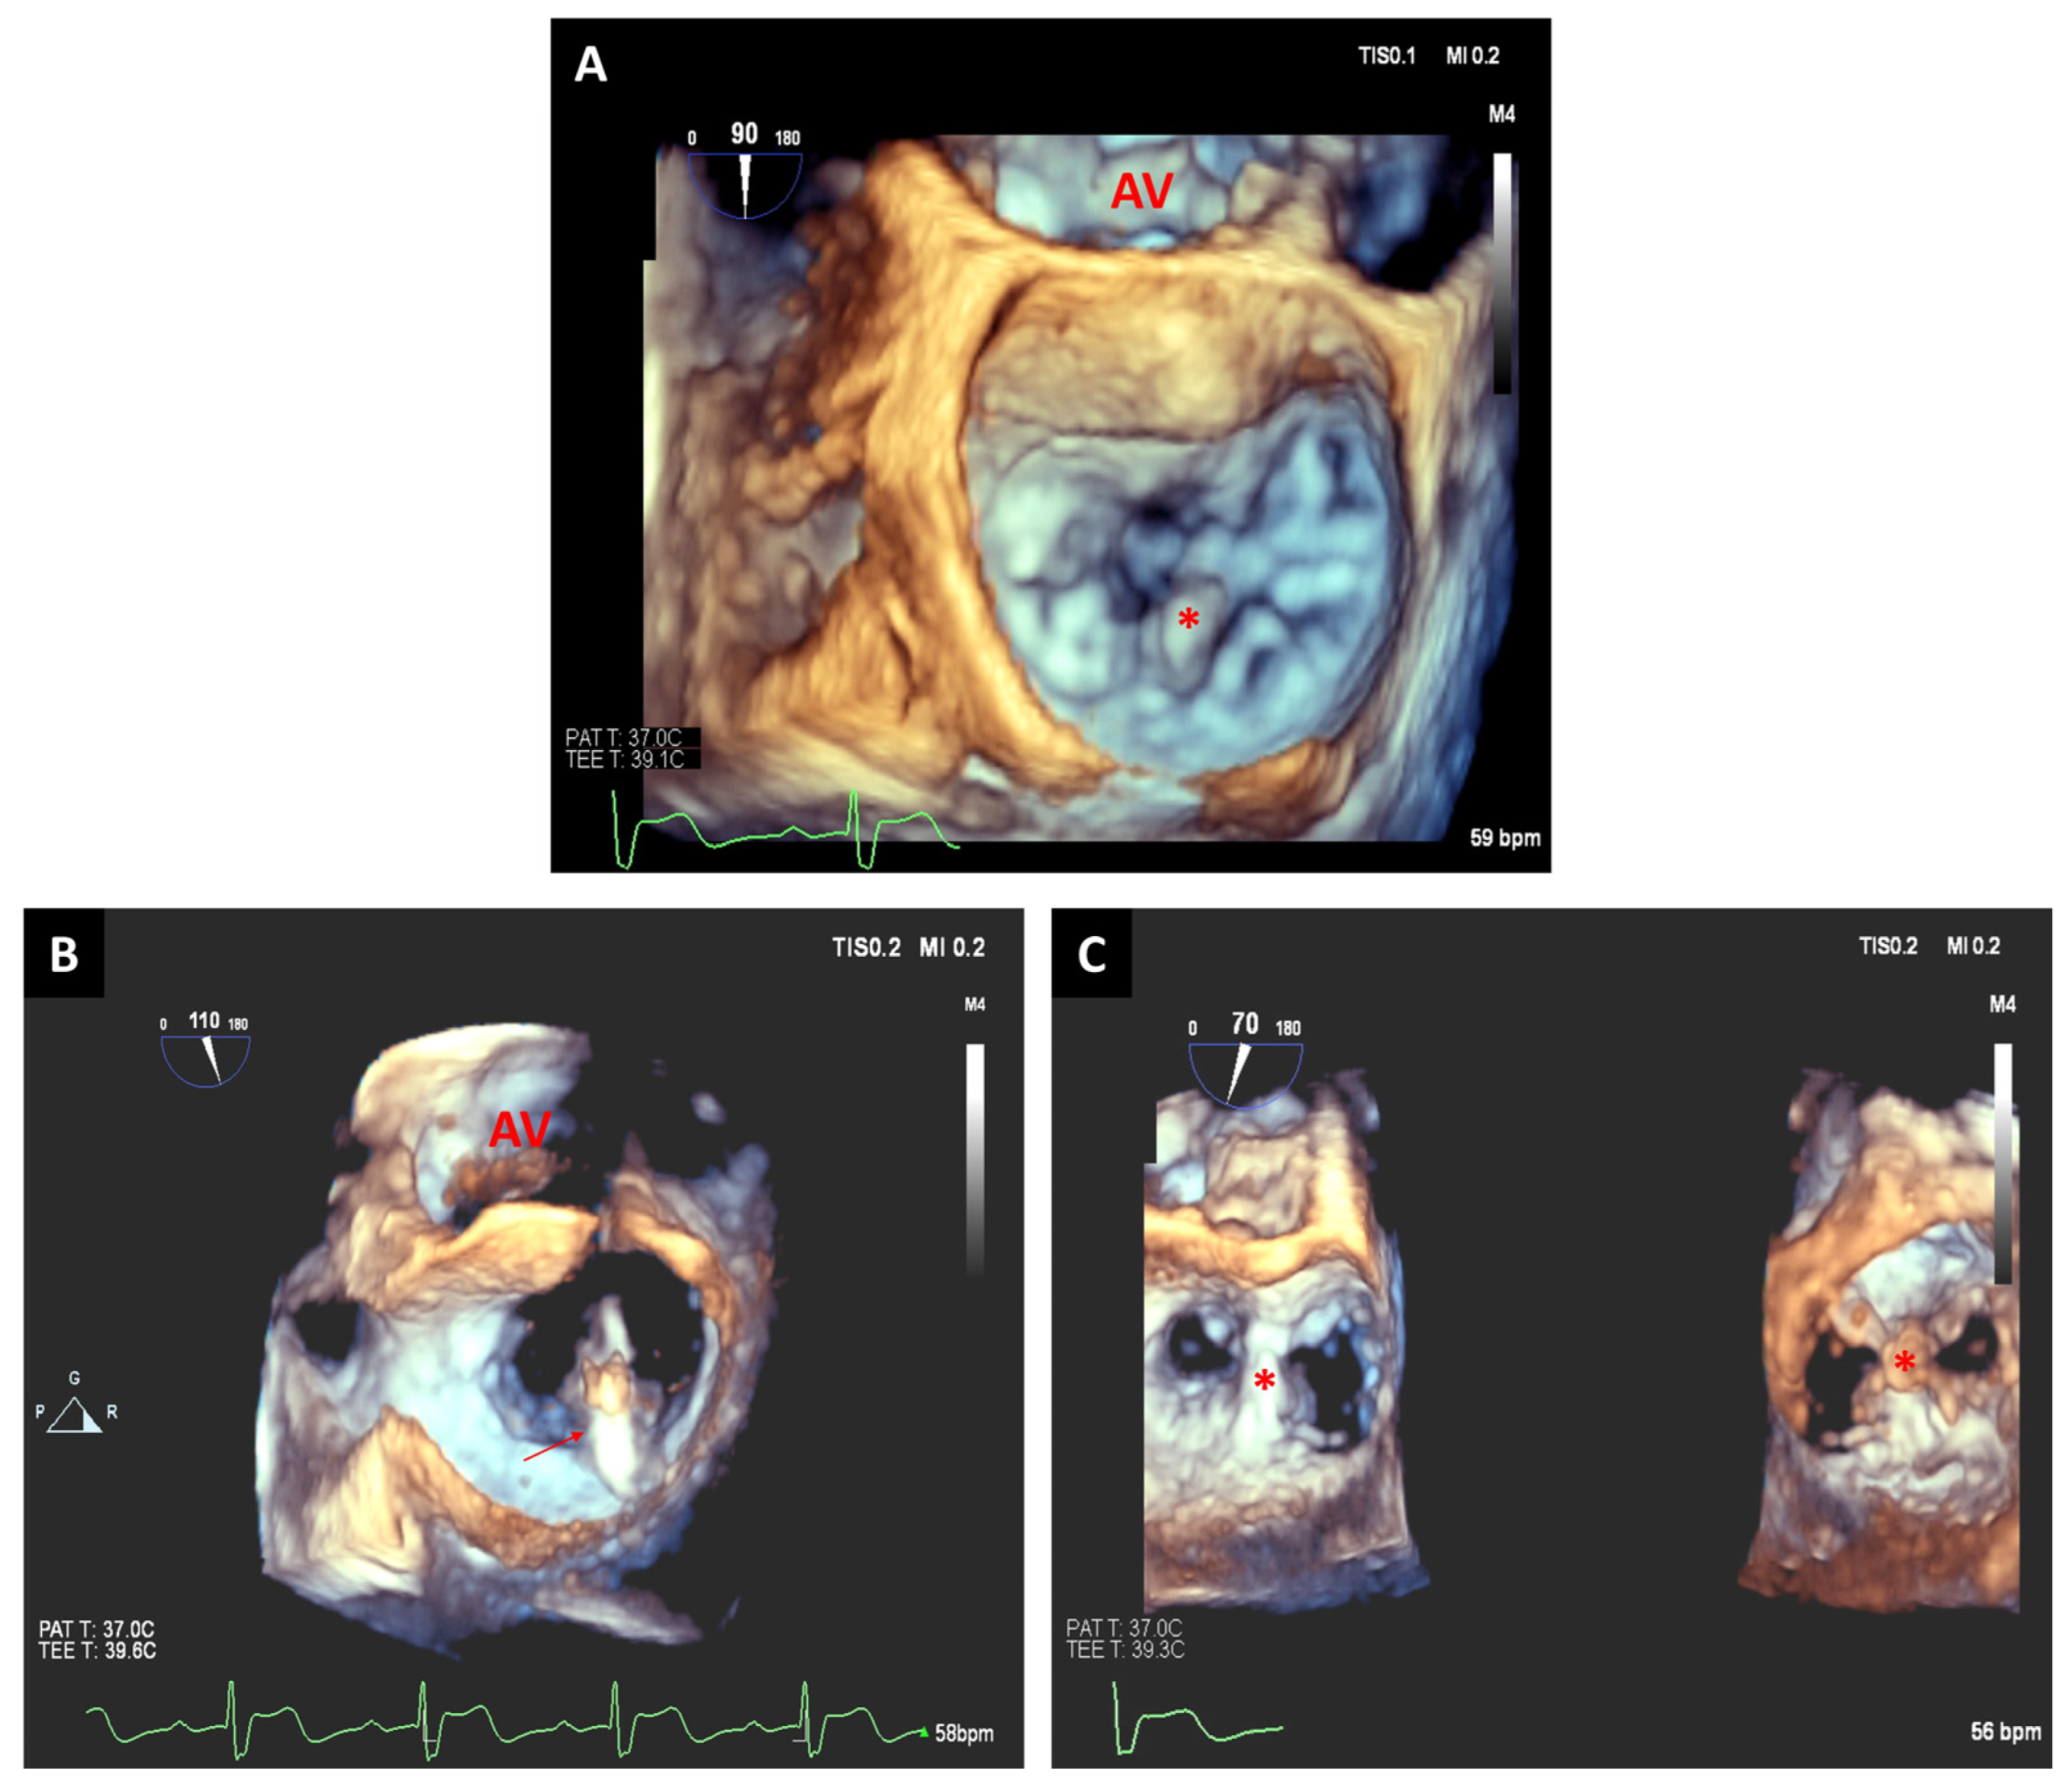

3.1. Transcatheter Aortic Valve Replacement